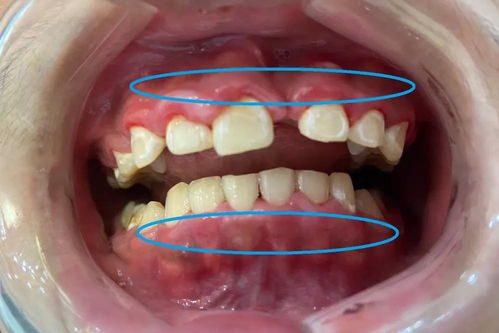

而潔治術(shù)這是我們經(jīng)常了解清潔牙齒的方式——洗牙,洗牙通常是牙齒表面出現(xiàn)牙結(jié)石的情況才會(huì)通過洗牙的方式做牙齒清潔,這些出現(xiàn)牙結(jié)石的牙齒主要是牙齦以上的牙齒,因?yàn)檠例l以下的牙齒單純靠洗牙無法清潔,這里就用著我們題目所說的齦下刮治術(shù)了。 齦下刮治術(shù)是對牙齒的進(jìn)行清潔的方式,它主要針對的是牙齦下方的牙石和牙菌斑。

在牙齒健康的情況下,牙根是被牙齦緊緊包裹的,牙根深處是無法長出牙菌斑和牙結(jié)石的,但是如果出現(xiàn)了牙周炎,細(xì)菌和臟東西就會(huì)深入牙根底部形成牙菌斑和牙結(jié)石。這種位于牙齦深處的牙菌斑和牙結(jié)石,無法單純的依靠刷牙和洗牙來去除,這時(shí)就需要齦下刮治術(shù)來將這些東西全部去除。

齦下刮治術(shù)不僅是去除牙齦深處的牙結(jié)石和牙菌斑,并且能夠在消炎藥的配合下,使剝離開來的牙齦重新包裹到牙根上,使牙齒更加的健康。 哪些人需要做齦下刮治術(shù)呢? 要不要做齦下刮治術(shù)?我們自己說的不算,不能認(rèn)為自己想對牙齒進(jìn)行深層清潔就擅自的要求自己要做齦下刮治術(shù)。